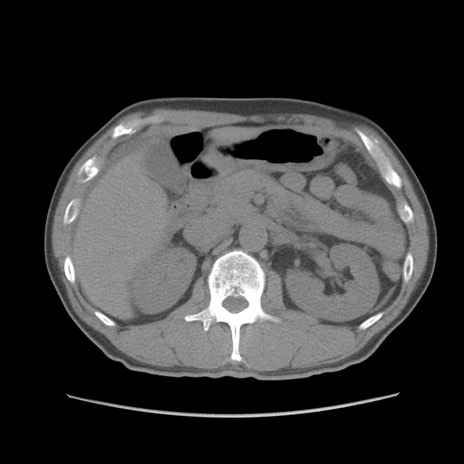

症例56 CT(横断像)

脂肪ウインドウ